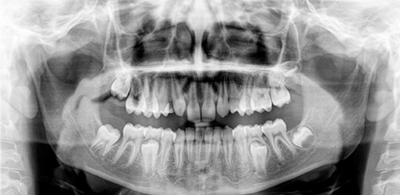

Cirurgias dentárias e

dos maxilares